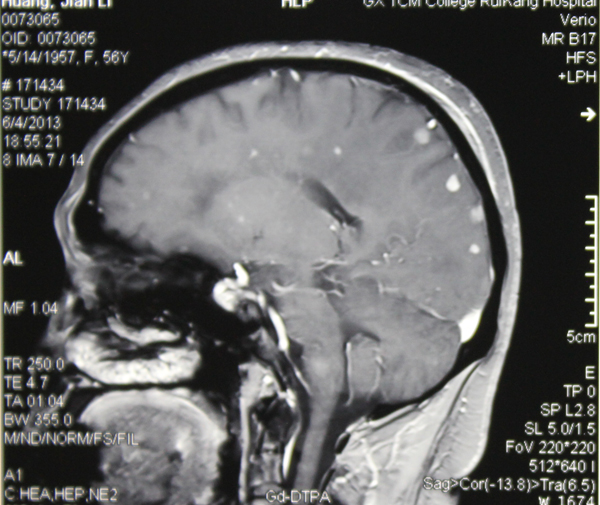

对于桌面上近一尺厚从各家医院带来的检查报告单和影像胶片,朱医生直言:整整花了一个下午才看完。从脑部CT片上可以看到黄阿姨的大脑星罗棋布地分布着点点白斑,盛医生说,各种报告都提示脑部存在病变,却不能明确病变性质。

眼看着阿姨的病情愈加严重,神经外科发挥集体的力量,多次讨论,翻阅大量资料,最终认定黄阿姨脑部患上了炎症疾病,极有可能是真菌感染,那些白斑和白点就是感染的部位。

抗真菌感染治疗前,黄阿姨脑部布满点点真菌

治疗一个月后,大部分感染已消失或缩小。